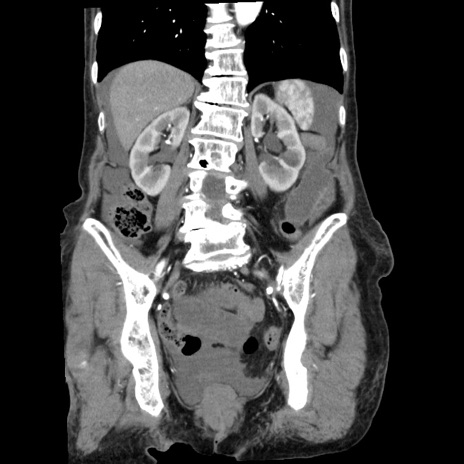

症例1(冠状断像)

【症例】80歳代女性

【主訴】腹痛

【現病歴】8時間前から腹痛あり来院。

【既往歴】糖尿病、脂質異常症、子宮体癌にて子宮全摘術

【身体所見】意識清明・会話良好だが腹痛で苦悶様、全腹部にわたって反跳痛と圧痛あり

【データ】WBC 13600、CRP 0.14、LDH 224、CK 90